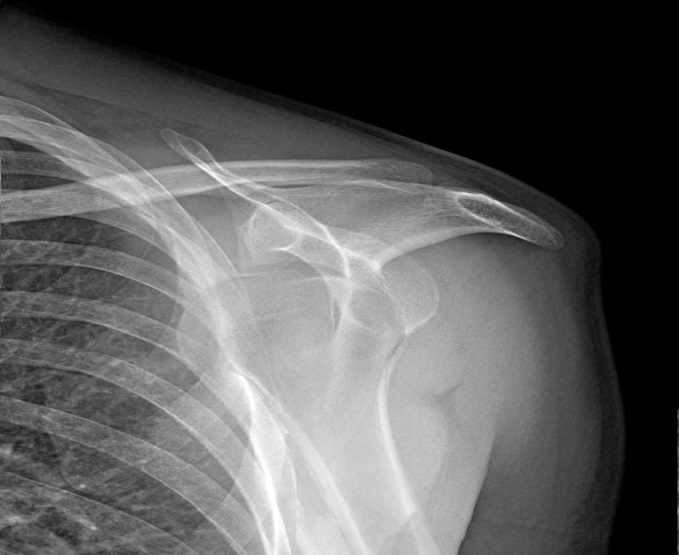

Tuğberk Baştürk , Furkan Kaya , Mehmet Duran